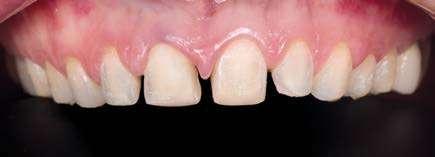

PROTOCOLOS DE AUTOTRASPLANTE POSEXTRACCIÓN: ¿INMEDIATOS

O DIFERIDOS?

El autotrasplante dental se está convirtiendo en una opción predecible en la odontología restauradora contemporánea. Sin embargo, las condiciones del alvéolo receptor pueden variar notablemente según el momento de la pérdida del diente y el tipo de diente a extraer. El objetivo de este artículo es presentar protocolos de autotrasplante posextracción basados en la planificación digital y describir los criterios de selección para cada una de las diversas opciones.

Introducción

El autotrasplante consiste en la extracción de un diente de su posición original y su posterior colocación en una posición distinta de la arcada dentaria del mismo paciente (Natiella y cols. 1970). Para realizar este procedimiento quirúrgico se pueden utilizar dientes donantes que estén erupcionados, dientes impactados o parcialmente impactados, independientemente del grado de formación radicular (Plotino y cols. 2020). Además, el autotrasplante puede realizarse tanto en situaciones posextracción inmediata como en alvéolos que hayan sido previamente preparados de forma quirúrgica (Abella y cols. 2021a).